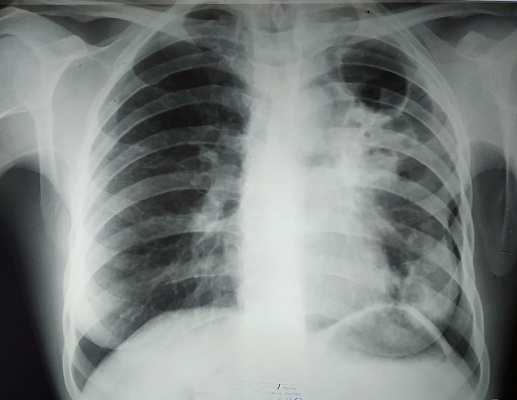

Фото: wiki